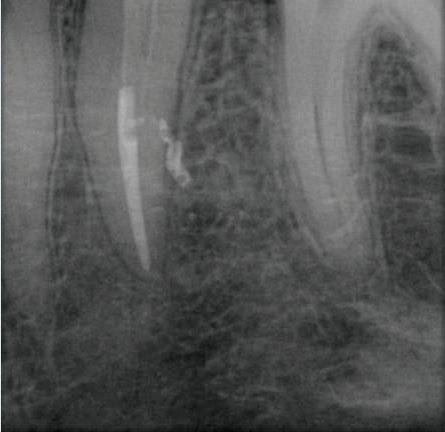

6: Präoperatives Röntgenbild Zahn 26, Fall 2. Karies unter einer früheren Kompositrestauration in Nähe der Pulpahöhle. – Abb. 7: Periapikales Röntgenbild mit mesial abgewinkeltem Röntgenstrahl zur Überprüfung der korrekten Obturation des abgetrennten zweiten mesiobukkalen Kanals nach der Behandlung. – Abb. 8: Postoperatives periapikales Röntgenbild.

Abb.

In den mesiobukkalen und zweiten unabhängigen mesiound distobukkalen Wurzelkanälen wurde die Feile 15/.03 (HyFlex EDM) verwendet, gefolgt von den nächsten Größen 10/.05 und 20/.05. Der palatinale Wurzelkanal wurde in der gleichen Reihenfolge aufbereitet sowie zusätzlich mit Feilen der Größen 25/~ (HyFlex EDM OneFile) und 40/.04. Der Endo­Motor wies mit einem langen Signalton auf das Spülen vor dem Fortschreiten der Feile hin. Dies geschah häufiger in den zweiten mesiobukkalen und distalen Wurzelkanälen, deren Aufbereitung sich aufgrund der engen und gekrümmten Kanalanatomie schwieriger gestaltete. Nach einer abschließenden Spülung und Trocknung mit passenden Papierspitzen erfolgte die Obturation mit trägerbasiertem thermoplastischem Guttapercha (Abb. 7 und 8).